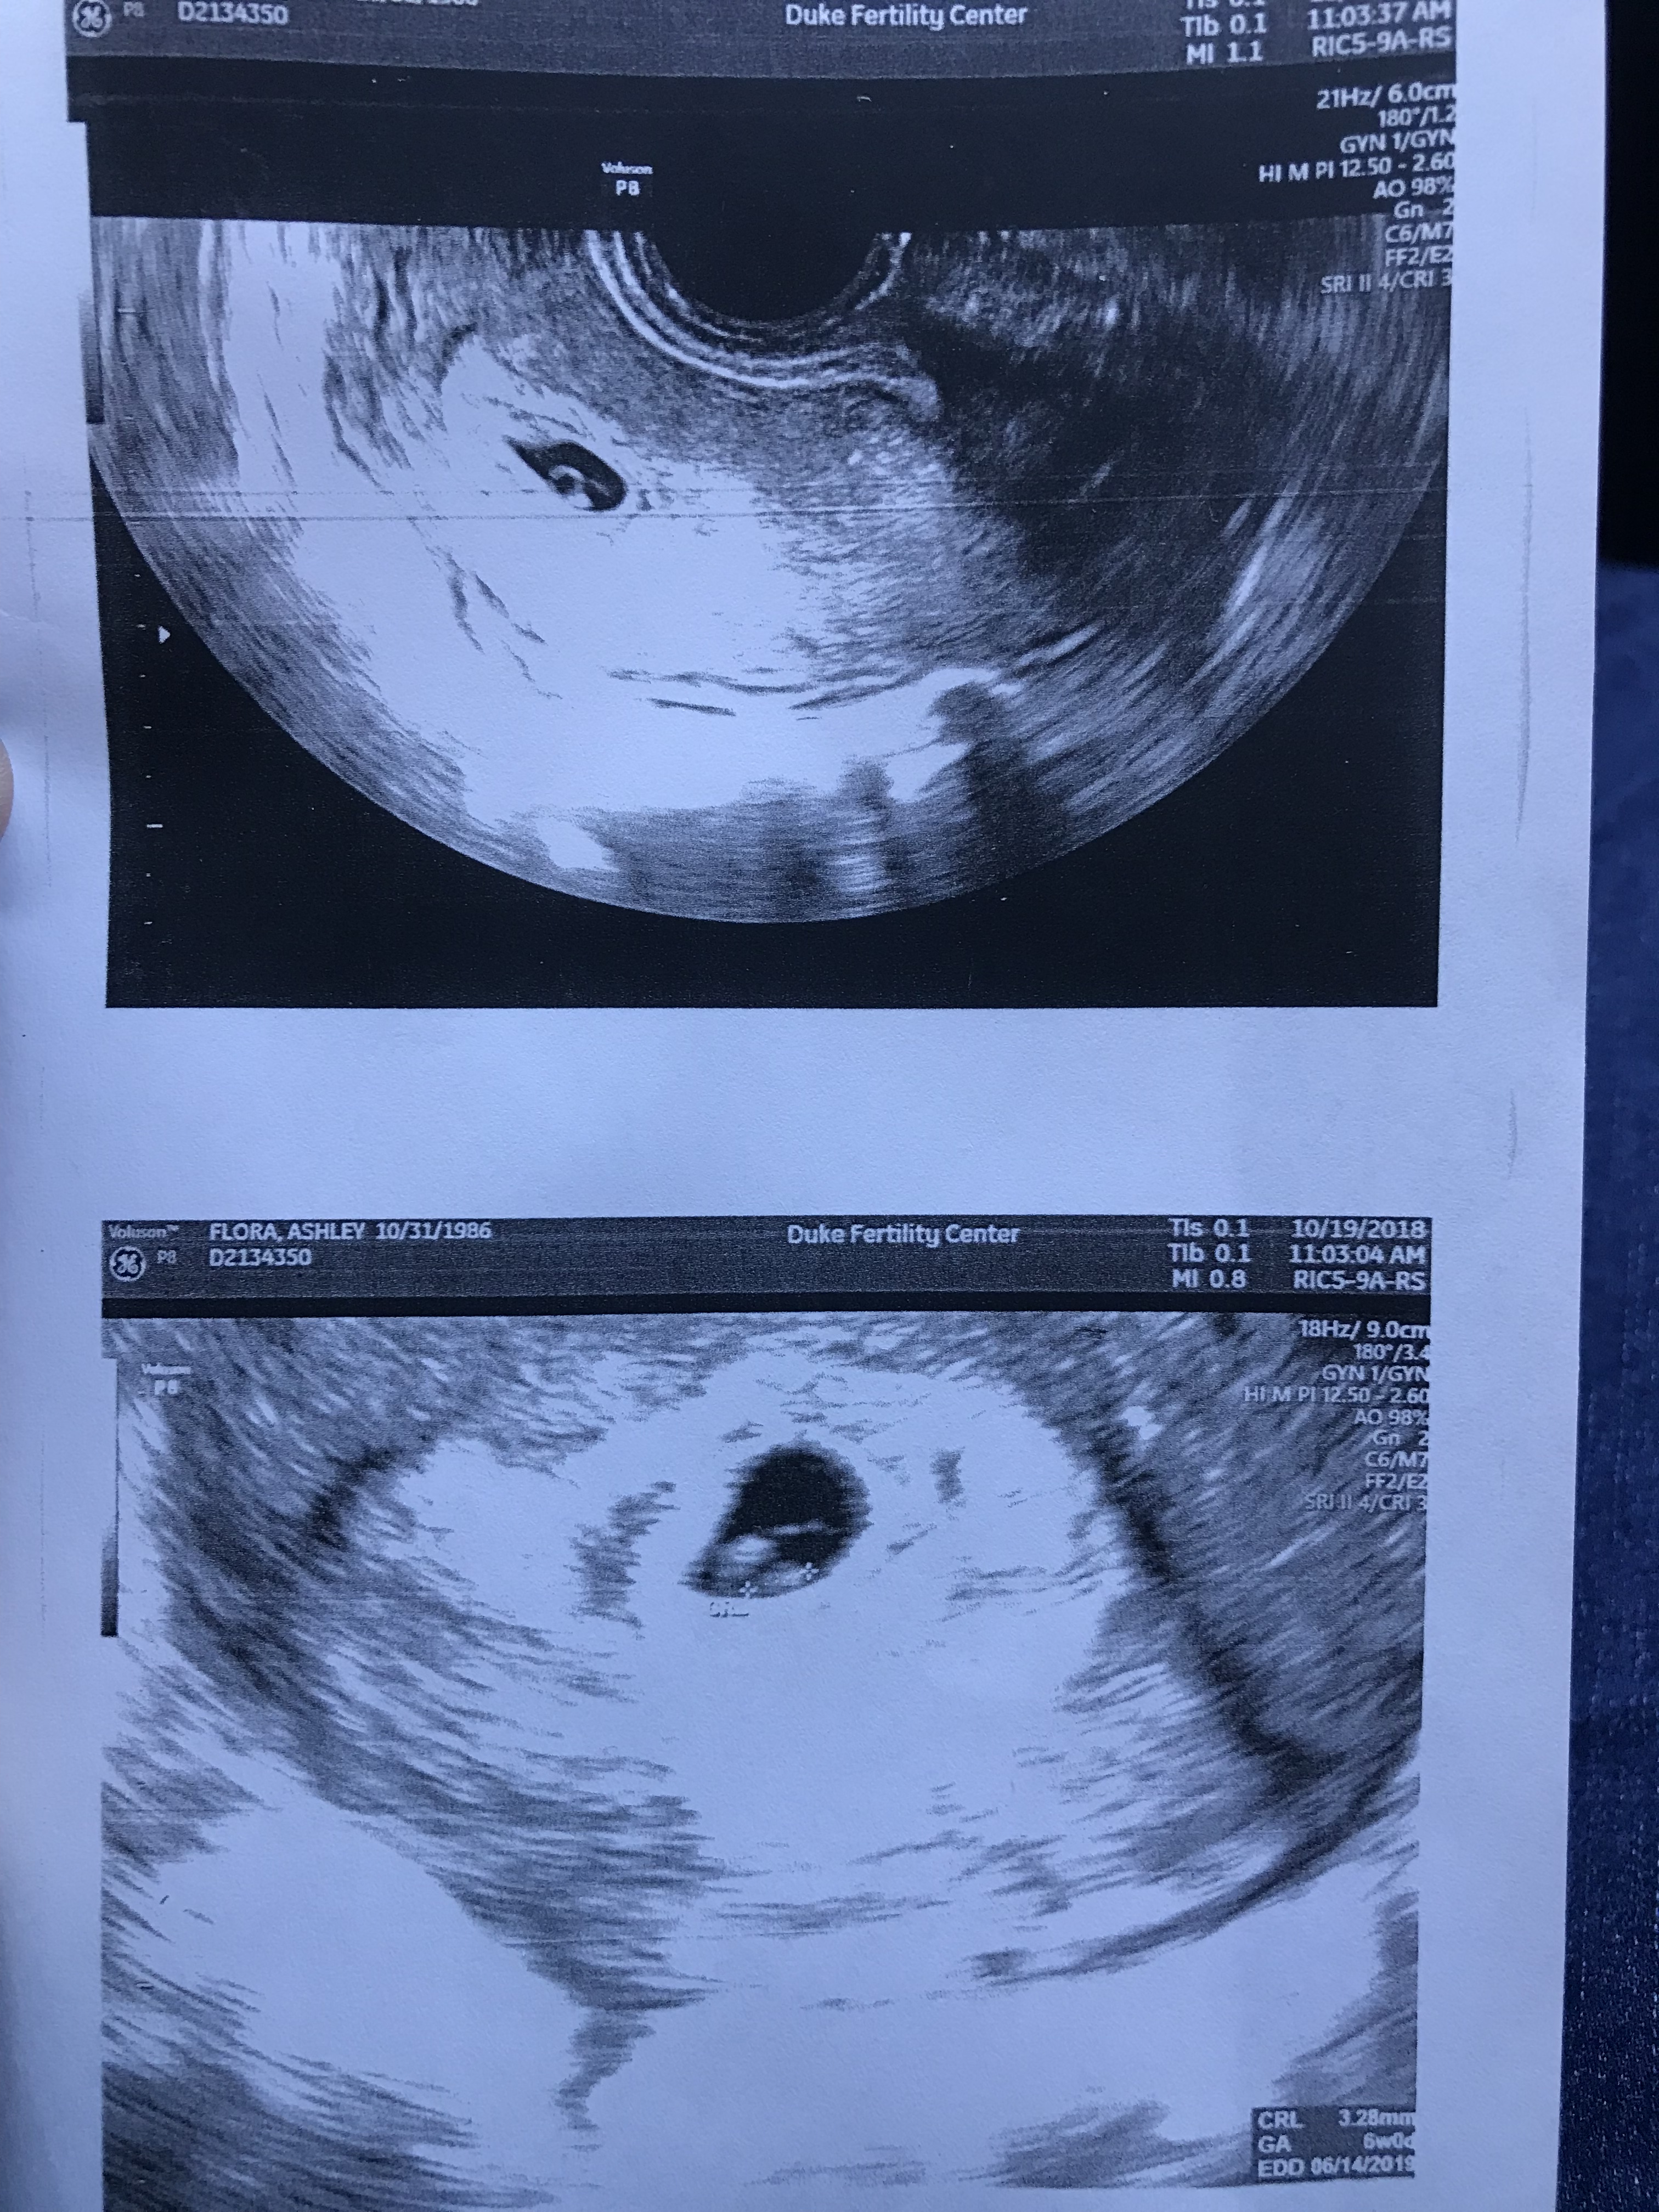

We were 3 weeks away from trimester 2. 3 weeks away from announcing. 11 weeks pregnant. See images of the excitement before this story unfolds. Our little bean was so loved by many from the beginning. Parents planning to be grandparents, siblings planning to become aunt and uncles. Close friends planning to meet this bundle of joy.

Ultrasound comes in, with two nurses to witness. The DR. does another ultrasound. This time shows me. The baby was measuring a week smaller than it should have been. No blood flow through the umbilical cord and no heartbeat. Baby was face down… so much bigger too. I could see a head, side of a face, arms, legs, feet, hands… but nothing was beating… just like that. Our world ended. With the ultrasound wand still in there I burst into tears hysterically. 3 people in the room rushed up to me the nurses and the dr and just hugged me while I wept.

Everything about the hospital visit was smooth and super private. The dr didn’t want me remembering anything of this experience so they did put me completely under for the procedure. They kept the privacy curtain up the entire time during pre op and post op. The Dr came in and did one last ultrasound to confirm. We were praying for a miracle but there were none to be found. This time the baby wasn’t face down which made the image in my mind better. However, this was done again without my husband back there yet. That’s the one thing I would have changed. You need your spouse there for that. They deserve just as much to see that. (We are asking for images for my husband).